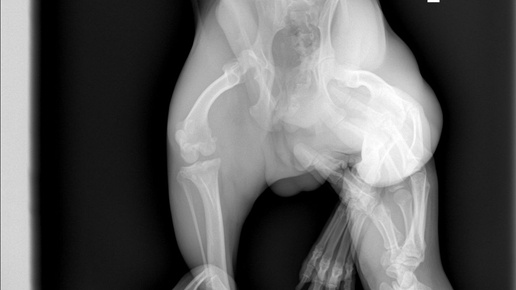

Выпадение тазобедренного сустава (также называемое вывихом бедра или дислокацией) — это патологическое состояние, при котором головка бедренной кости выходит из вертлужной впадины таза. Это приводит к нарушению функции конечности, сильной боли и хромоте. Такая травма чаще встречается у собак средних и крупных пород (лабрадоры, овчарки, ротвейлеры), но может возникнуть и у мелких пород вследствие травм или врожденных патологий. Для подтверждения диагноза ветеринар проводит: Применяется при незначительных смещениях и включает: Необходимо при повторных вывихах или тяжелых повреждениях...

Руководство по лечению вывиха тазобедренного сустава у кошек и собак Классификация по направлению смещения: наиболее типичный – краниодорсальный, затем каудовентральный (головка смещается вниз и назад), реже – каудодорсальный и краниовентральныйvetusklinika.ruvetopedia.fr. При краниодорсальном вывихе нога приподнята и повернута наружу, при каудовентральном – может быть опущена и повернута внутрь. Тазобедренный сустав – шаровидный (ball-and-socket), образован головкой бедренной кости и вертлужной впадиной таза. Стабильность обеспечивают: суставная капсула, круглая связка головки (ligamentum teres), вертлужная губа (лабрум), тазовые кости (задний край вертлужной впадины)dergipark...